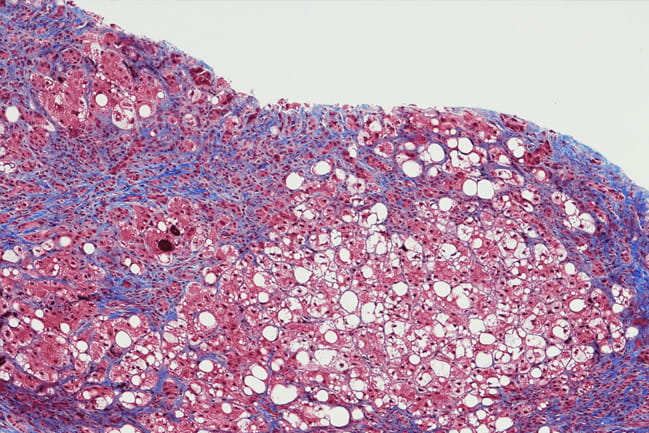

microscopic image of liver cells with fibrosis

Characterized by stiff and hardening tissue known as fibrosis, systemic sclerosis – also known as scleroderma – can affect the skin as well as other organs. Most research has focused on the pathology and starting point of fibrosis, but researchers at the Medical University of South Carolina are focusing on what causes it to spread.

Carol Feghali-Bostwick, Ph.D., is a Distinguished Professor in MUSC’s division of rheumatology and immunology and the SmartState and Kitty Trask Holt Endowed Chair for Scleroderma Research as well as the lead author on the paper. She points to three hallmarks of scleroderma, which is considered an autoimmune connective tissue disorder: vascular anomalies, immune system dysregulation and fibrosis. With fibrosis, cells make too much extracellular matrix components like collagen. Too many of these proteins accumulate and cause the tissues to thicken. Thick or hardened lungs for instance are unable to expand and collect enough oxygen.